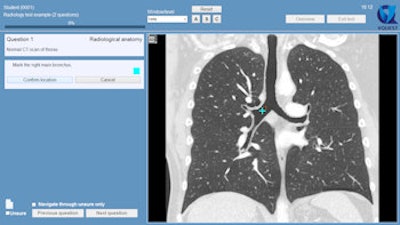

Example of an "indicate question" in VQuest. The student is asked to mark an anatomical structure in the volumetric image. Students can scroll through the image, change contrast settings manually or with the preset window/level menu, or change viewing direction by clicking the buttons (A, S, and C). The teacher decides which manipulation tools the students are allowed to use during the test or for a particular question. All images courtesy of Dr. Cécile Ravesloot.

In the volumetric test questions, for example, the participants could change viewing directions by pushing buttons, for instance to view sagittal or coronal views, and after contrast administration they could alter the contrast settings (abdomen, bones, lungs) by choosing preset window levels.